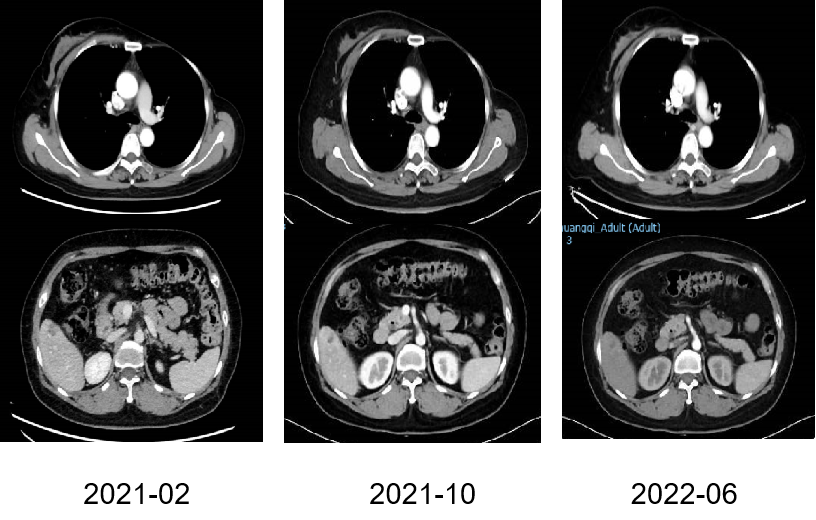

图4